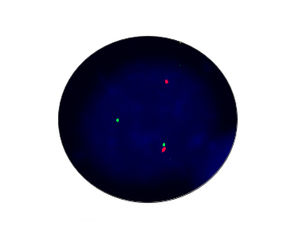

- FISH

1.非小細胞肺がんでは、inv (2) (P21; P23)が融合遺伝子EML4-ALKの分子サブユニットを形成し、標的薬Crizotinibのターゲットとなっています。

2.2010年の非小細胞肺がん診療ガイドラインでは、ALK阻害剤の効果予測のために、新たにEML4-ALKの評価項目が追加されました。